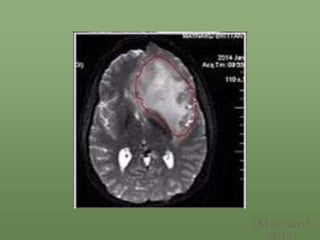

• On January 1, 2014, she was diagnosed with stage 2 astrocytoma and had a partial

craniotomy and a partial resection of her temporal lobe.

• The cancer returned in April 2014, and her diagnosis was then elevated to stage 4

astrocytoma with a prognosis of six months to live.